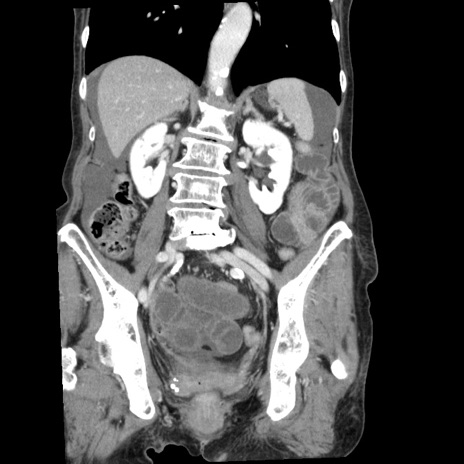

症例1(冠状断像)

【症例】80歳代女性

【主訴】腹痛

【現病歴】8時間前から腹痛あり来院。

【既往歴】糖尿病、脂質異常症、子宮体癌にて子宮全摘術

【身体所見】意識清明・会話良好だが腹痛で苦悶様、全腹部にわたって反跳痛と圧痛あり

【データ】WBC 13600、CRP 0.14、LDH 224、CK 90